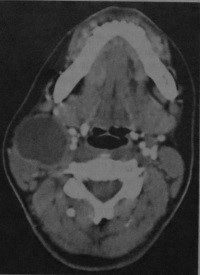

Признаки бранхиогенной (боковой) кисты шеи на снимках КТ и МРТ

- МРТ, КТ.

- Кистозное образование (10-25 HU) латеральнее нервно-сосудистого пучка (до 10 см в диаметре)

- Смещает поднижнечелюстную железу кпереди и медиально, грудино-ключично-сосцевидную мышцу - кзади и латерально

- Часто расположена рядом с углом нижней челюсти, иногда в окологлоточном пространстве или кпереди от нервно-сосудистого пучка

- Кровоизлияния в полость кисты и перегородки в ней встречаются редко

- Утолщение стенки и ее усиление после введения контраста наблюдается только в случае инфицирования кисты.

- Интенсивность сигнала на Т1 -взвешенном изображении зависит от содержания белка или крови (низкое содержание - гипоинтенсивный сигнал, высокое - гиперинтенсивный)

- Высокая интенсивность сигнала на Т2- взвешенном изображении

- Объемное образование с четкими границами, не инфильтрирует окружающие ткани

- Интенсивное усиление стенки после введения гадолиния наблюдается только при инфицировании кисты.

- Не накапливающая контраст гладкостенная киста, расположенная ме- диальнее нервно-сосудистого пучка, кпереди от грудино-ключичнососцевидной мышцы и позади поднижнечелюстной слюнной железы.

Инфицированная бранхиогенная киста. КТ с контрастированием: киста на уровне правого угла нижней челюсти. Наблюдается утолщение и усиление стенки кисты, а также снижение плотности в центре образования. Грудино-ключично- сосцевидная мышца смещена кзади и лате рально, нервно-сосудистый пучок - медиально.

МРТ, Т2-взвешенное изображение без контрастирования: бранхиогенная киста в левой поднижнечелюстной области. Интенсивность сигнала в центре кисты значительно повышена, сигнал от стенки кисты имеет промежуточную интенсивность. Грудино-ключично-сосцевидная мышца смещена кзади и латерально, нервно- сосудистый пучок - медиально.